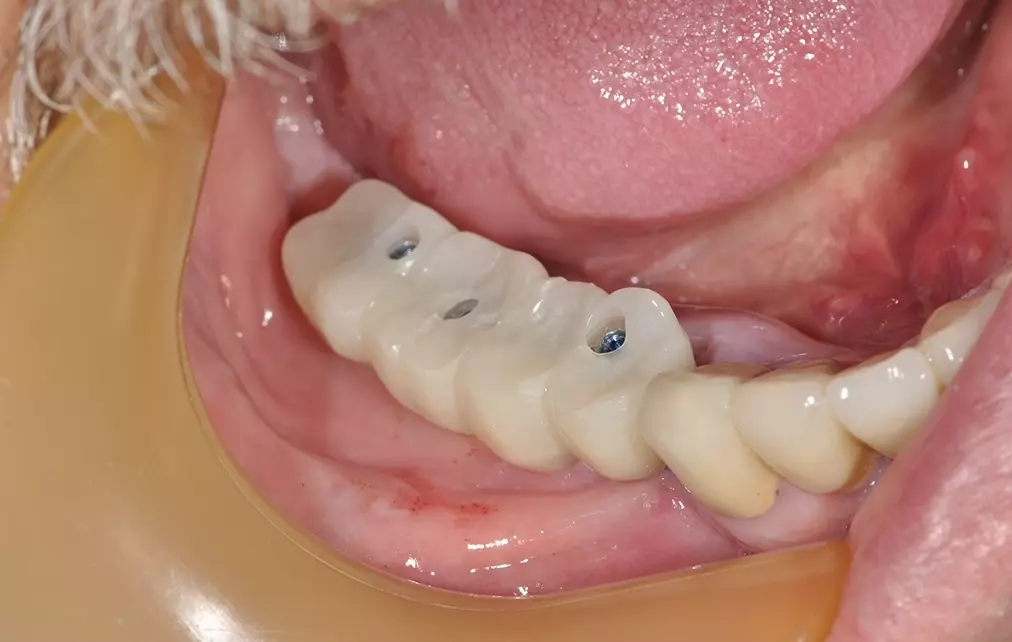

Es kann ein einfaches, unkompliziertes Einschrauben des endgültigen Gerüstes mit der nur ganz leicht auf okklusalem Kontakt gearbeiteten PMMA-Verblendung erfolgen (Abb. 11, 12). Dieses Vorgehen erlaubt die mit vielen Vorteilen verbundene Sofortversorgung innerhalb von 24 Stunden mit einem endgültigen Zahnersatzgerüst. Bei jeder prothetischen Maßnahme wird zudem immer auf Mukosaniveau gearbeitet und nicht mehr auf Knochenniveau – ein Komfort für den Patienten und ein Benefit für den krestalen Knochenanteil.

Dres. Petschelt